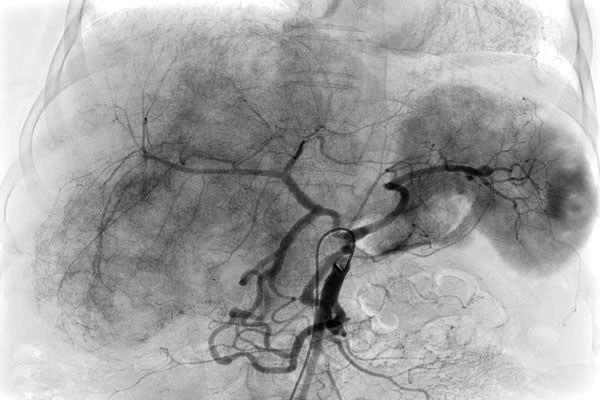

患者,女,62歲,以肝癌肝內(nèi)廣泛轉(zhuǎn)移收住入院,已無(wú)外科手術(shù)切除機(jī)會(huì),只能行介入化療栓塞術(shù)(TACE)。術(shù)中血管造影發(fā)現(xiàn)為肝臟供血的腹腔干已經(jīng)閉塞,導(dǎo)管無(wú)法進(jìn)入肝動(dòng)脈行介入化療栓塞術(shù),介入手術(shù)只能終止。由于已無(wú)其它治療方法,介入化療栓塞術(shù)終止,意味著患者只剩下1-2個(gè)月的生命??吹交颊吆图覍賹?duì)生命的渴望和對(duì)我們介入醫(yī)生的高度信任,我們不甘心就此放棄手術(shù)和延長(zhǎng)患者生命的機(jī)會(huì)。任小軍副主任反復(fù)研究血管造影圖像,見患者腸系膜上動(dòng)脈有側(cè)枝循環(huán)供應(yīng)到肝動(dòng)脈,仍有希望通過細(xì)小迂曲的側(cè)枝循環(huán)繞到肝動(dòng)脈進(jìn)行肝癌化療栓塞術(shù),但路途遙遠(yuǎn),操作復(fù)雜,手術(shù)時(shí)間長(zhǎng),醫(yī)生接受射線輻射大幅增加,并且成功的可能性很小,但是不嘗試,就沒有成功的機(jī)會(huì)。與家屬深入溝通后,任小軍副主任和任雪會(huì)副主任醫(yī)師反復(fù)耐心操作微導(dǎo)管,在技師和護(hù)士的高度配合下,導(dǎo)管終于成功進(jìn)入肝固有動(dòng)脈和肝右動(dòng)脈,對(duì)患者成功實(shí)施了介入化療栓塞術(shù),術(shù)后攝片和CT掃描顯示栓塞的碘油和化療藥大量沉積于肝臟腫瘤內(nèi),持續(xù)殺滅著腫瘤細(xì)胞?;颊咝g(shù)后反應(yīng)輕,恢復(fù)良好,現(xiàn)已出院。

這種腹腔干閉塞,通過腸系膜上動(dòng)脈側(cè)枝循環(huán)治療肝癌的病例少見,它技術(shù)難度大,需要深入插管到腸系膜上動(dòng)脈-回腸動(dòng)脈-胃十二指腸動(dòng)脈-肝固有動(dòng)脈-主要供血的肝右動(dòng)脈,導(dǎo)管在腸系膜上動(dòng)脈內(nèi)反復(fù)操作,出現(xiàn)腸系膜上動(dòng)脈夾層并引起腸梗死的風(fēng)險(xiǎn)大,手術(shù)時(shí)間長(zhǎng),介入醫(yī)生接受射線輻射多,一般都會(huì)終止治療。為了讓患者獲得最佳療效而延續(xù)生命,我們不放棄,敢創(chuàng)新,即使只有1%的希望也要付出100%的努力。對(duì)于一個(gè)醫(yī)生,沒有什么比延續(xù)患者生命更重要,沒有什么比延續(xù)患者生命更令人驕傲和自豪!